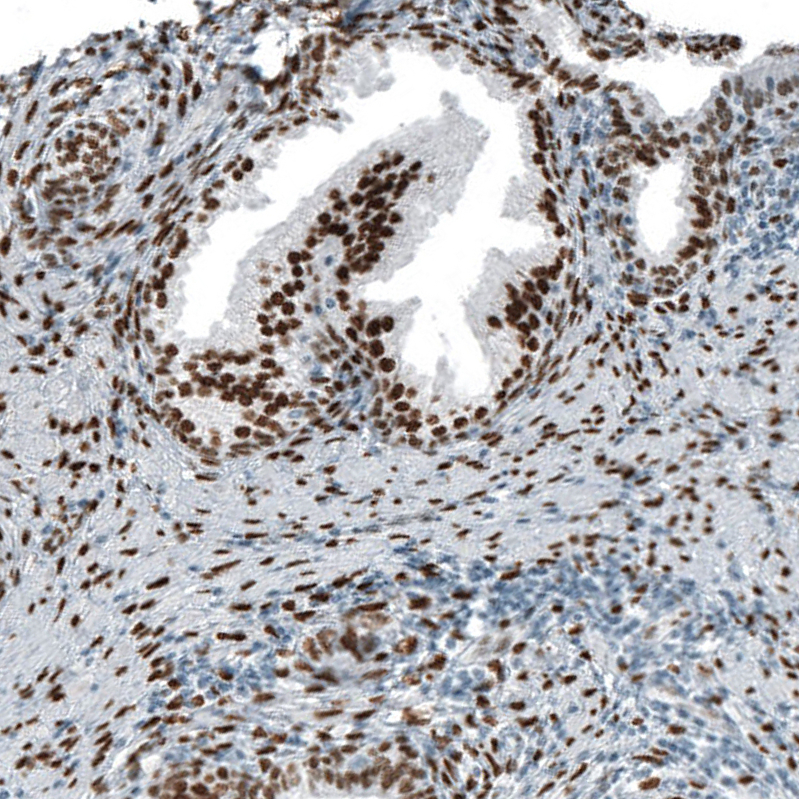

Immunohistochemistry analysis in human fallopian tube and cerebral cortex tissues using AMAb91547 antibody. Corresponding AR RNA-seq data are presented for the same tissues.